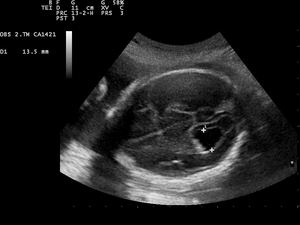

Ventriculomegaly

Ventriculomegaly is a brain condition that occurs when the lateral ventricles become dilated. In fetuses, the most common definition uses a width of the atrium of the lateral ventricle of greater than 10 mm.[1] This occurs in around 1% of pregnancies.[2] When this measurement is between 10 and 15 mm, the ventriculomegaly may be described as mild to moderate. When the measurement is greater than 15mm, the ventriculomegaly may be classified as more severe.[3] Enlargement of the ventricles may occur for a number of reasons, such as loss of brain volume (perhaps due to infection or infarction), or impaired outflow or absorption of cerebrospinal fluid from the ventricles. Often, however, there is no identifiable cause. The interventricular foramen may be congenitally malformed, or may have become obstructed by infection, hemorrhage, or rarely tumor, which may impair the drainage of cerebrospinal fluid, and thus accumulation in the ventricles. This diagnosis is generally found in routine fetal anomaly scans at 18–22 weeks gestation. It is one of the more common abnormal brain findings on prenatal ultrasound, occurring in around 1–2 per 1000 pregnancies.[4] In many cases of mild ventriculomegaly, however, there is resolution of ventriculomegaly during the pregnancy.

Although evaluation of lateral ventricles dimensions is decisive for establishing a diagnosis of ventriculomegaly, the shape of the ventricular system, including that of the frontal horns, is also important.[10]